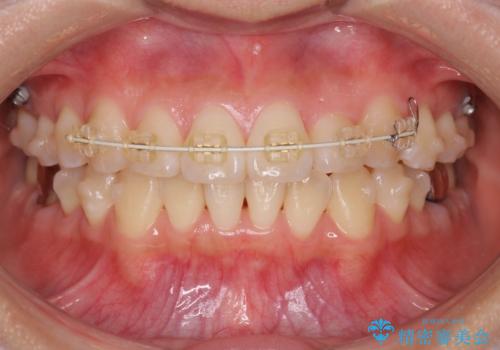

- 矯正装置

- インビザライン +部分ワイヤー矯正

マウスピース矯正システムインビザラインで歯の後方移動、咬合関係の修正を行ったのち、引っ込んでいる左上2をワイヤーを用いて短時間で引き出す治療計画としました。

部分ワイヤー矯正を行なったことで約3ヶ月という短期間で前歯を綺麗に並べることができました。